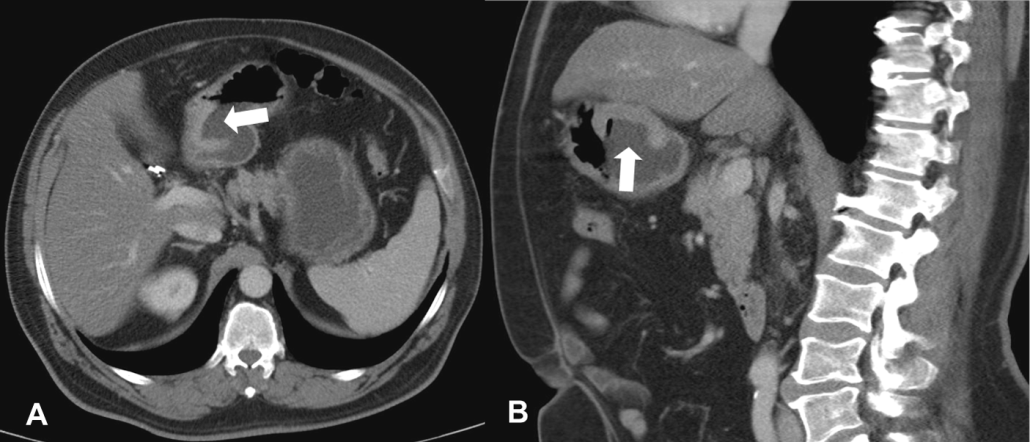

Thick tortuous folds or lobulated filling defects in the cardia or fundus. Right gastroepiploic artery inferiorly and left gastroepiploic artery and short gastric arteries superiorly fundus of the stomach. Results of surgical treatment of carcinoma of the esophagus and gastric cardia. The collection of cases presented here comprises only that material which is rare in our experience or quite new to us.

Cain jc jordan gl jr comfort mw gray hk. J am med assoc. The gas tric fundus is dened as the portion of the stomach craniad to the gastric car dia. Commonly accompanying this are abnormally dilated short gastric veins which pass from the splenic vein to encircle the gastric fundus and form gastric fundal varices.